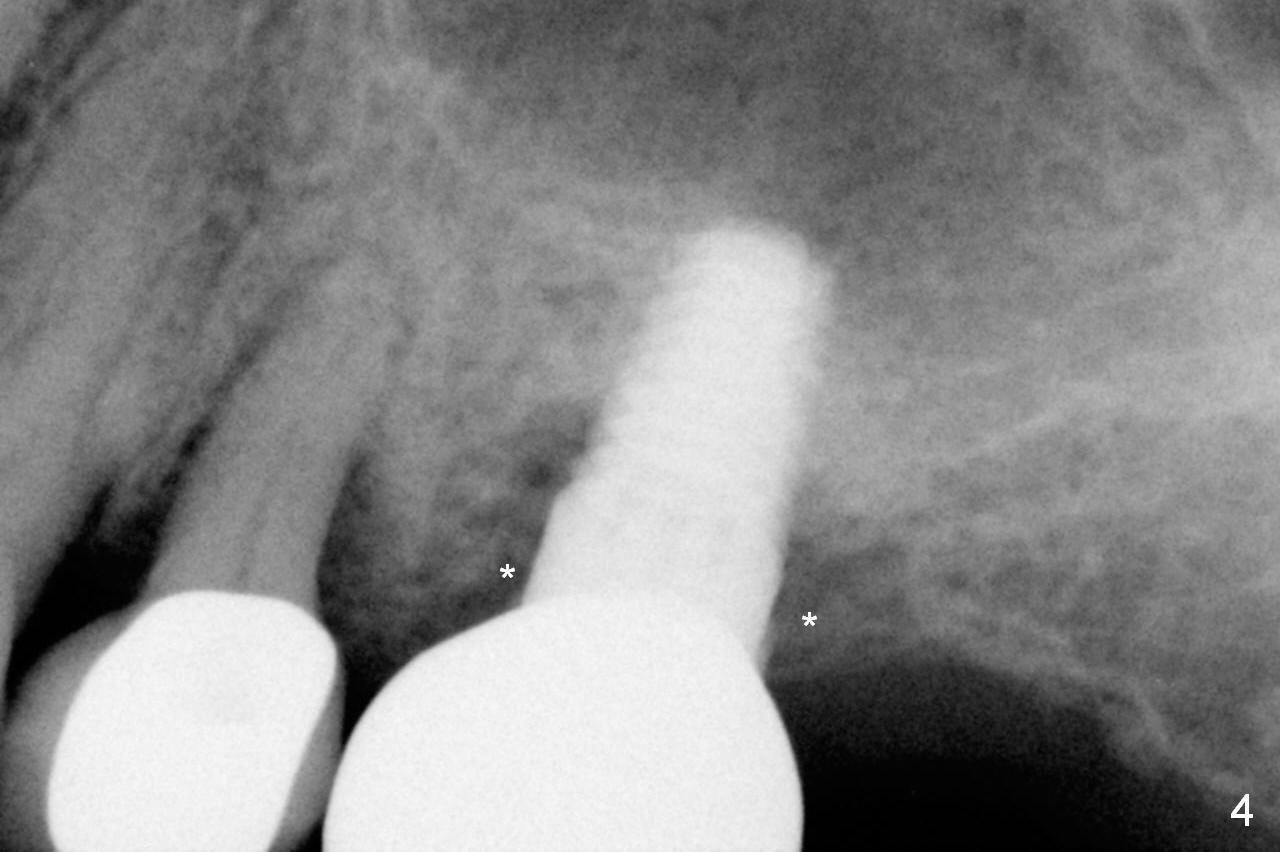

A 73-year-old woman is a possible bruxer with partial edentulism; the tooth #13 had increased periodontal ligament (pdl) space 4 years ago (Fig.1 *).  A 5x14 mm tissue-level implant is placed at the site of #14 (Fig.2).  The implant appears to be osteointegrated in 6 months (Fig.3).  There is crestal bone loss 8 months post cementation (Fig.4 *).  The persistent increased pdl at #13 is most likely associated with occlusal tramua from the tooth #19 (Fig.5 (13 months post cementation of #14)).  Three years post #14 cementation, the tooth #13 has mobililty II (Fig.6); bone density increases around the apical half of the implant (arrowheads).  Normally bone density is the highest coronally where functionality dictates.  This indicates the bone loss is getting worse at #14 as well.